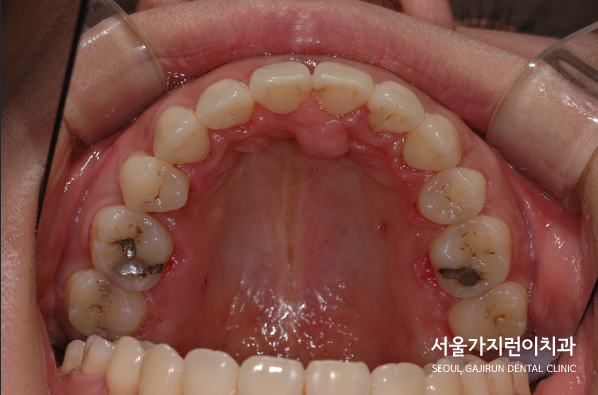

교정 전 환자분의 구강상태는 상악우측과 좌측의 위치상의 큰 차이를 눈으로도 확인할 수 있었는데요. 측면의 경우 상악의 뻐드러님도 육안으로도 확인할 수 있는데다 앞니의 벌어짐도 있어서 전체적인 교정이 필요한 상태였습니다. 씹는 면을 보면 전체적으로 비뚤어져 있다는 것을 확인할 수 있죠. 여기에 무턱까지 갖고 계셔서 환자분께서 명확한 치아교정 니즈를 갖고 계셨습니다. 그런데 환자분의 경우 치조골이 소실되었기 때문에 교정이 불가능하다는 답변을 이미 다른 곳에서 들은 바 있었는데요.